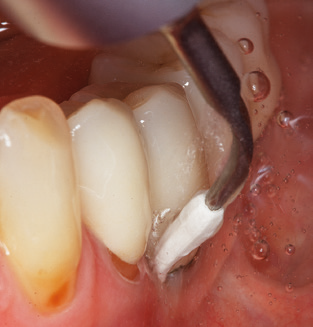

Nach der maschinellen Reinigung der Zahn­ und Implantatoberflächen erfolgt eine manuelle Instrumentierung der natürlichen Zahnoberflächen mit konventionellen Handinstrumenten. Bei der manuellen Reinigung ist insbesondere auf einen korrekten Anstellwinkel, eine ausreichende Schärfe, eine gute Abstützung und auf eine von apikal nach koronal gerichtete Arbeitsweise der Kürette zu achten. Zur Nachinstrumentierung der Implantatkonstruktionen sollten entweder Titan­ oder Carbonküretten verwendet werden (Abb. 8). Ergänzend zum Einsatz von Ultraschallgeräten können in der Erhaltungstherapie auch Pulverstrahlgeräte genutzt werden. Dabei ist jedoch zu berücksichtigen, dass diese Verfahren nicht zum Entfernen harter Beläge geeignet sind und daher die Verwendung von Hand­ oder Ultraschallinstrumenten nicht komplett ersetzen können. Abschließend erfolgt in jedem Fall eine mechanische Politur der zugänglichen Zahn­ und Implantatoberflächen mit Polierkelchen und Polierpasten (Abb. 9).

Abb. 4: Für das Sondieren an dentalen Implantaten sind biegsame, millimeterskalierte Sonden empfehlenswert (z.B. Colorvue Kit PCV11KIT6, Hu-Friedy). – Abb. 5a und b: Eine gerade Arbeitsspitze (1P, W&H Dentalwerk Bürmoos GmbH) ist universell für die Instrumentierung natürlicher Zähne geeignet. – Abb. 6: Für die Bearbeitung schwer zugänglicher Bereiche der Zahn- und Wurzeloberflächen (z.B. Furkationen) bieten sich gebogene Arbeitsspitzen (3Pr/3Pl, W&H Dentalwerk Bürmoos GmbH) an. – Abb. 7: Die spitz zulaufende sechseckige Implantatreinigungsspitze (1I, W&H Dentalwerk Bürmoos GmbH) ermöglicht eine atraumatische und effiziente Reinigung der Kronen- und Abutmentoberflächen. – Abb. 8: Für die manuelle Instrumentierung der Implantatoberflächen sind Titan- oder Carbonküretten geeignet.